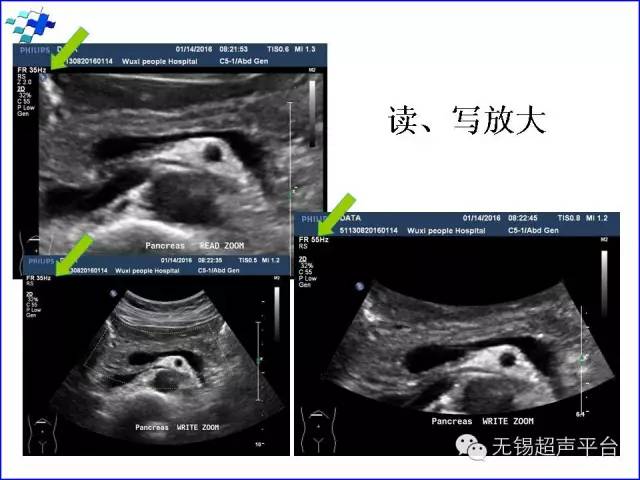

宽度(width):图像的宽度越大局部取样线密度越稀疏,帧频越低。图像放大(zoom):感兴趣区域的放大功能,对相对较小的结构和快速运动的结构的评价有很大价值,如瓣膜的形态学。